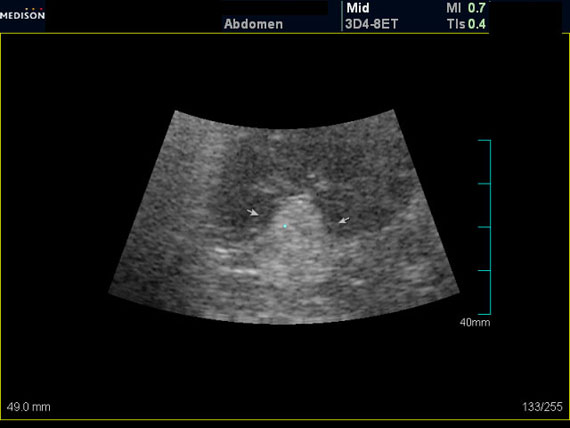

Женщина 50 лет. Жалоб нет. Обследование перед поездкой в санаторий по поводу дисфункции гепатобилиарной системы.

Случайная находка в нижней трети левой почки (не в полюсе, а по задне-медиальной поверхности).

ПО УЗ-семиотике образование соответствует ангиомиолипоме (AML). По правилам в таких случаях необходимо выполнить КТ, доказать преимущественно жировой состав опухоли, затем проводить УЗ-наблюдение.

Согласен. Именно с таким диагнозом (ангиомиолипома) отправил на КТ. Особенностью случая ИМХО является заметный "выход" образования за контур почки (на 2/3 объема).

При ультрасонографии ангиомиолипома выглядит как округлое образование без капсулы с однородной внутренней эхоструктурой и четкими контурами; эхогенность ее чаще всего равна или чуть выше эхогенности перинефральной клетчатки [7]. Значительно реже эхогенность ангиомиолипом может быть равна эхогенности почечной паренхимы; такие опухоли состоят почти полностью из гладкомышечной ткани [8]. Иногда позади ангиомиолипомы может определяться слабая акустическая тень.